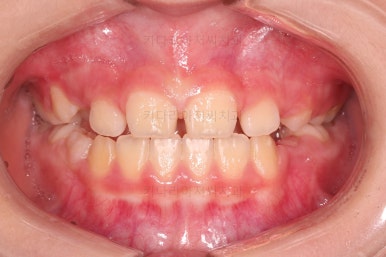

초진 시 입안의 모습입니다.

아래쪽 치열이 전반적으로 윗니보다 앞쪽에 위치한 전형적인 앵글씨 3급 부정교합인데요.

어금니에서부터 앞니까지 아랫니가 윗니보다 앞쪽에 위치하네요.

특히 앞니는 아랫니가 윗니보다 나와있는 "반대교합" 상태였고요.

또한 위아래로 겹침이 없고 떠있는 "개방교합" 상태였어요.

즉, 앵글씨 3급 부정교합 - 반대교합 - 개방교합 등 굉장히 복합적인 교합의 문제를 가진 환자였습니다.